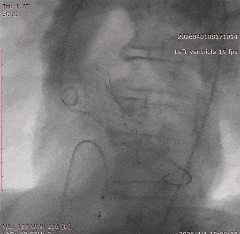

冠脉治疗后一周,张老先生整体状态平稳,进入主动脉瓣置换阶段。团队从股动脉建立通道,将人工瓣膜送至主动脉瓣位置。结合术前评估结果和术中情况,这次手术未进行球囊预扩张,而是直接完成瓣膜释放。

术中,因患者主动脉弓形态较复杂,器械通过一度受阻。团队根据术中情况及时调整策略,最终顺利完成过弓、跨瓣和瓣膜释放。造影及经胸超声显示,瓣膜位置理想、功能良好,左右冠脉血流通畅,未见瓣周漏及血管并发症。

▲根部造影

▲血管扭曲预塑形导丝支撑不足

▲更换导丝后过弓过瓣

▲初始定位

▲左右重合位评估

▲左冠切线位评估

▲最终瓣膜造影

▲入路检查